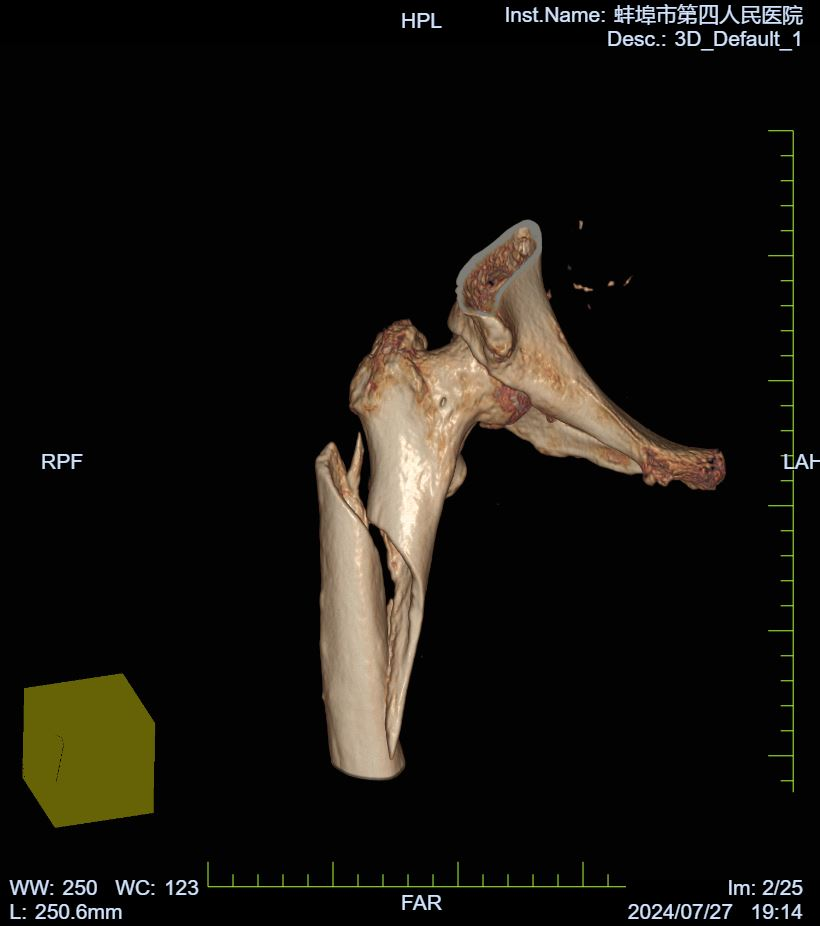

患者范奶奶今年70多岁了,因在家中不慎摔倒导致右侧大腿严重受伤,出现剧烈疼痛和外观畸形,活动受到限制,幸无皮肤破损及出血现象。伤后,范奶奶未出现头晕、头痛、心慌或气促等并发症,鉴于疼痛难忍,为求进一步治疗,她来到蚌埠市第四人民医院(市康复医院)骨科寻求帮助,经过门诊拍片后确诊为“右侧股骨干骨折”,随即安排入院治疗。

入院后,我院骨科团队迅速为范奶奶完善了相关检查,建议其卧床休息,同时采取抗炎止痛、患肢抬高牵引制动等综合治疗措施。值得注意的是,范奶奶右侧股骨有多次骨折病史,并接受过多次手术治疗。目前,她上次右侧股骨下段骨折的内固定装置尚未取出。针对这一复杂情况,我院骨科联合手术室(麻醉科)、护理部等多学科专家,对范奶奶的病情进行了全面而细致的评估与研讨,共同制定了周密的麻醉及手术方案。

2024年8月3日,由骨科李贵主任主刀,在骨科团队的辅助下,顺利为范奶奶实施了精准的右侧股骨切开内固定装置去除术(针对部分螺钉)及股骨髓内钉内固定术。手术过程中,骨科与手术室(麻醉科)医护人员紧密协作,手术圆满成功。范奶奶术后状况稳定,且经C臂机透视确认右侧股骨髓内钉复位及内固定位置均理想,最终平安返回病房。